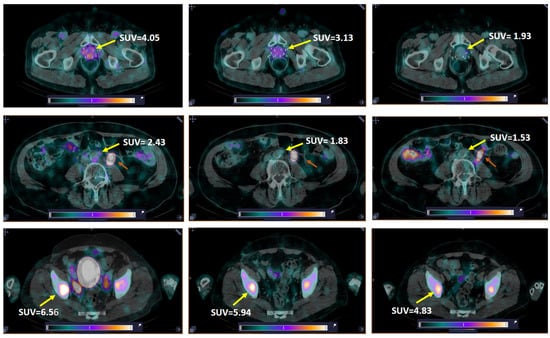

LNMs were visualized in 2 out of 12 patients with known lesions (16.7%), and BMs in 2 out of 6 patients with known lesions (33.3%) (Figure 7). Additionally, activity uptake in BMs was visualized in two patients without known bone involvement according to CT. Patients with visualized LNMs and BMs were administered 80 or 120 µg of peptide. The SUVmax values for LNMs and surrounding tissues for individual patients were lower than for primary tumors in both groups injected with 80 and 120 µg of peptide, while for BMs, the group injected with 80 µg had a higher SUVmax than for primary tumors (Table 1). Nevertheless, the ratios for SUVmean in metastatic lesions to surrounding tissues were suitable for visualization: for LNM, 1.97–3.49 for 80 µg and 2.40–2.61 for 120 µg; for BM, 3.97–9.81 and 1.72–2.53, respectively.

Figure 7. SPECT/CT images of PCa patients 2 h after injection of [99mTc]Tc-DB8. The foci of increased [99mTc]Tc-DB8 uptake (yellow arrow, SUVmax) are visualized (a) in the prostate (Patient 16); (b) in the paraaortic lymph node on the left (Patient 10); and (c) in the left ilium (Patient 10). A linear relative scale (normalized at the maximum activity in the image SUVmax from 0 to 5.0) is applied.